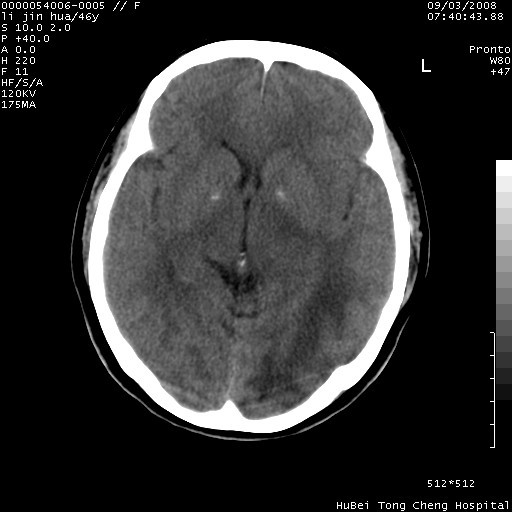

以下是引用panyishengct在2008-9-6 1:47:00的发言:[br]病史?[br]左侧枕/顶叶见一等/低混杂密度占位,壁完整,厚薄较均匀,其前方似有一类似小病灶,周围有水肿带,请结合病史考虑,脓肿可能,不排外转移瘤或胶质瘤,建议增强扫描。